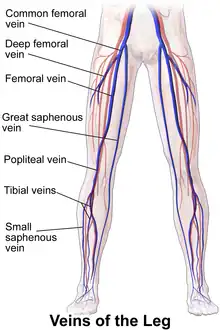

Great saphenous vein. Deep dissection. Anterior view. Illustration depicting veins of the leg including great saphenous vein (anterior view).

Illustration depicting veins of the leg including great saphenous vein (anterior view).